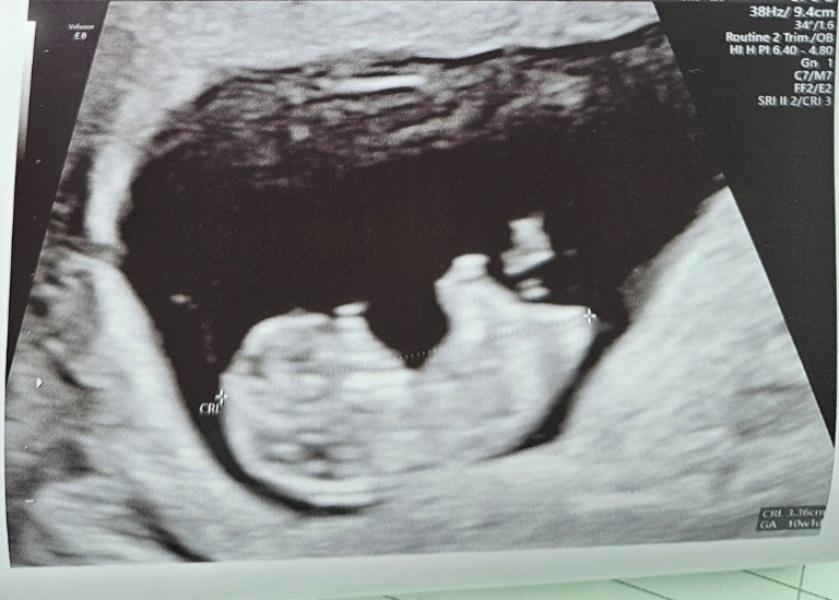

Oh my god, girls. I completely forgot to message in here! We had our NIPT test last week at 10+1. We have a live and kicking baby. Measuring exact and wriggling around. The relief ❤️ just waiting on the results now and we're finding out the gender!